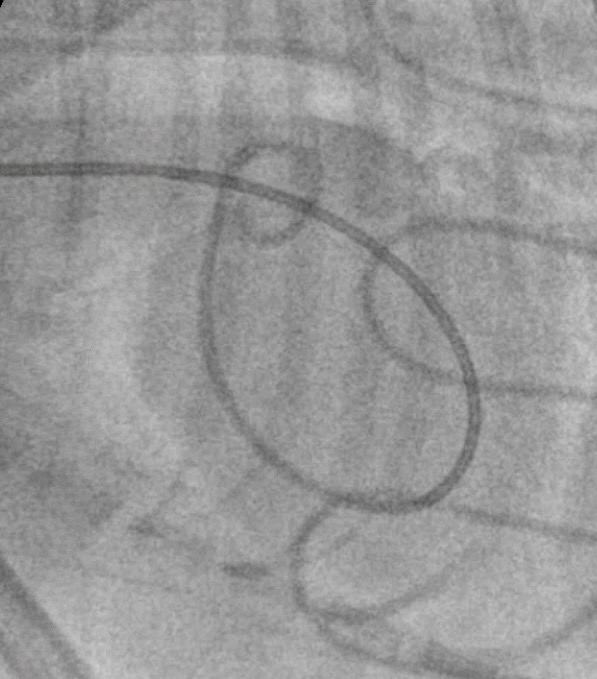

Following extraction, pulmonary artery pressures were directly measured using a catheter.

Catheterisation is the gold standard to diagnose pulmonary hypertension.